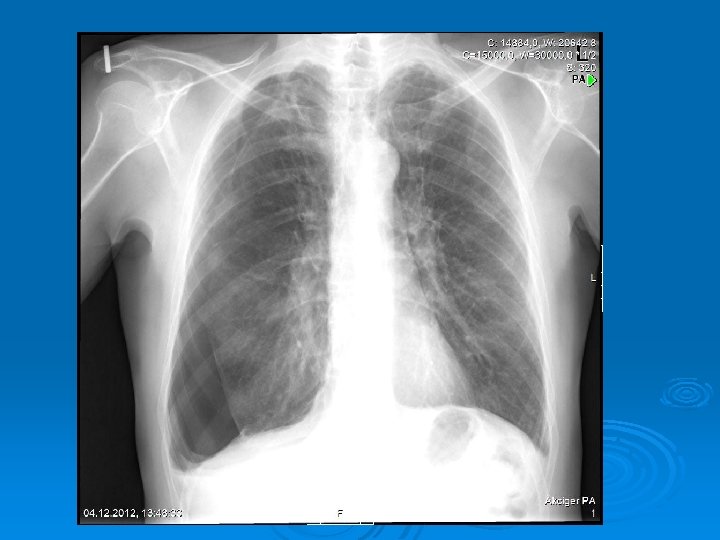

Radiology The fluid initially accumulates in the more dependent recesses of the thoracic cavity forming a Damoiseau Line Ø 200 -300 ml of pleural effusion can be detected on standard chest radiograph as blunting of the costophrenic angle Ø

Massive pleural fluid often shifts the mediastinum to the opposite side

Accumulation of the fluid between the diaphragm and the interior surface of the lung (Subpulmonic fluid): The hemidiaphragm appears to be elevated (Widening the distance between the top of the gastric bubble and the top of the left hemidiaphragm (>2 cm) and flatened Blunting of the posterior costophrenic angle on the lateral chest radiograph